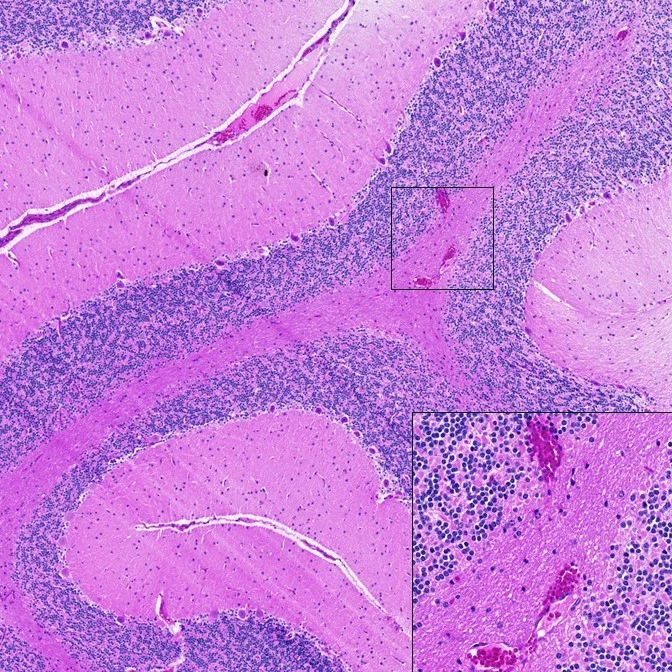

该团队的初步工作显示SARS-CoV-2感染导致了大脑中的少量出血。这些初步发现是在大流行病的早期出现的,以至于与这项工作无关的专家都持怀疑态度。在那个时候,这些神经系统的症状还没有在人类病人身上发现。

Fischer说:“你看到了病理学,它是如此明显,如此深刻。我观察中枢神经系统已经有几十年了,这么久以来,你知道什么时候有些东西看起来不正常,似乎与感染相一致。”

Fischer和她的团队又花了一年时间来验证这些最初的发现,因为其他研究人员开始在人类身上找到类似神经症状的证据。对照动物进行了研究,并完善了研究方案,以确认那些最初发现的大脑变化与冠状病毒感染直接相关。

除了少量出血,研究人员还发现了严重的广泛的大脑炎症和神经元损伤。 Fischer说,神经损伤与呼吸道疾病的严重程度没有关系。这意味着许多动物只表现出轻微的COVID-19症状,但仍然经历了神经系统的损害。